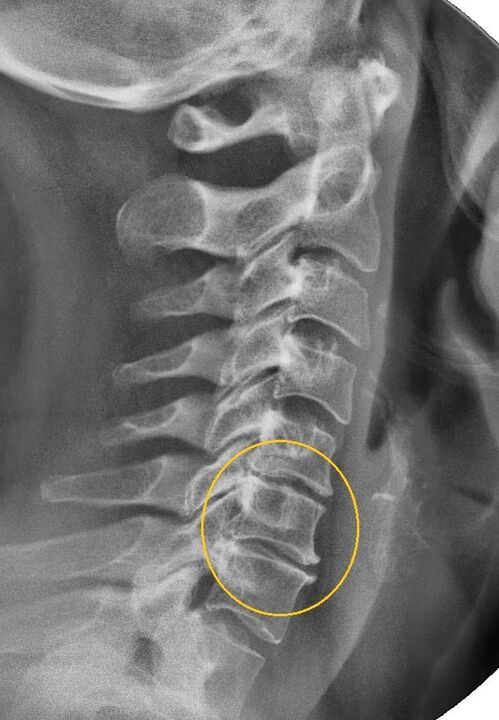

El procedimiento de diagnóstico más informativo es la radiografía. Las patologías de 1er grado corresponden a la 1ª o 2ª etapa radiológica. Las imágenes resultantes visualizan signos típicos de la enfermedad.

Etapas radiológicas de la osteocondrosis cervical de primer grado. Signos característicos

Etapa 1 Cambios menores en la curvatura de la columna en la región cervical, que afectan a uno o más segmentos.

Etapa 2 Ligero engrosamiento de los discos intervertebrales, deformación de las apófisis uncinadas, enderezamiento de la lordosis, crecimientos menores de las estructuras óseas.

Manifestaciones de osteocondrosis de la columna cervical en radiografía.